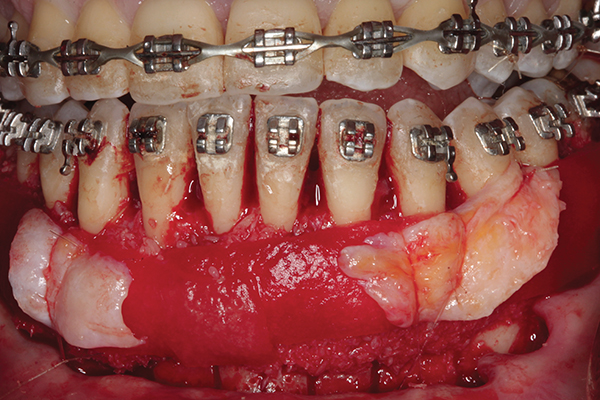

Fig 2. Full-thickness flap reflection. Note

dehiscence and fenestrations throughout. Orthodontic walls are limited to nonexistent.

Figure 2